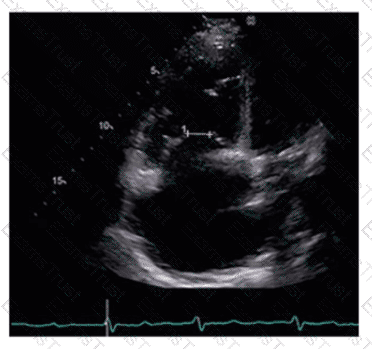

Which coronary artery territory is associated with the wall motion abnormality demonstrated in this video?